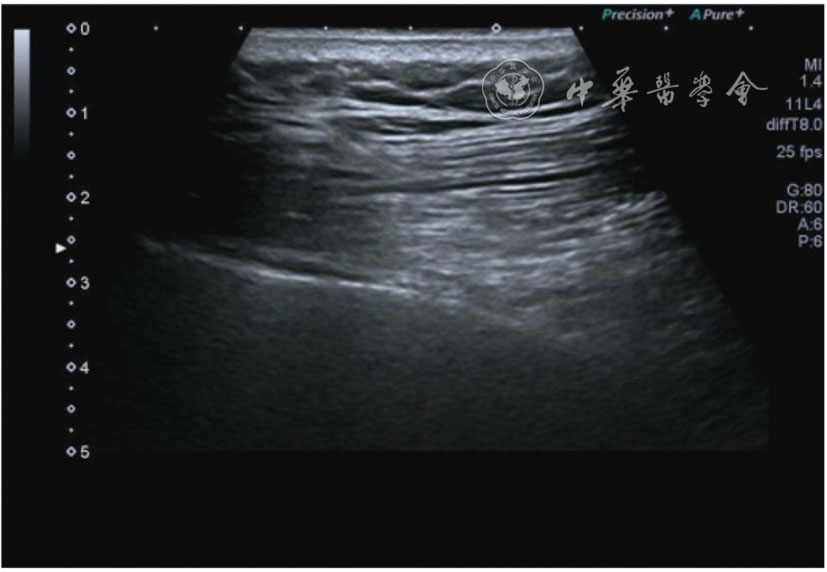

患者采取侧卧位,患肢在上,屈膝20°。应用10~18 MHz高频线阵探头,扫查深度1~3 mm。长轴和短轴结合双侧对比扫查。超声影像学所见:短轴可见卡压腓总神经近端增粗,面积增大;长轴可见腓总神经卡压处变细,其近侧肿胀、回声减低,而在卡压远侧则表现正常(图35);一些受压严重者可以出现神经周围积液,卡压神经部位的筋膜增厚(图36);受压神经内血流增加对临床诊断意义更大(图37);探头在病变神经处加压常可引起神经刺激症状。腓总神经支配的肌肉有失神经支配改变,表现为肌肉回声增高和肌肉萎缩(图38)。

图38 肌肉回声增强和肌肉萎缩超声图像